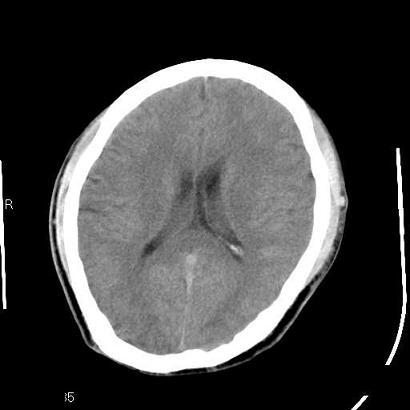

男,39岁,外伤来诊,老师们看看枕骨是什么病

枕内隆突左缘板障区示不规则囊状透亮区,颅骨内外板规整,无膨胀及缺损,周围无软组织肿块,考虑板障血管性病变,1.板障静脉湖,2.枕骨血管瘤(局部无膨胀性改变,无硬化环及钙斑影,故不太支持)。

蛛网膜颗粒压迹不会象这样有清晰的内板显示的!压迹压迹肯定是把内板压到板障里撒!各位老师同意不?